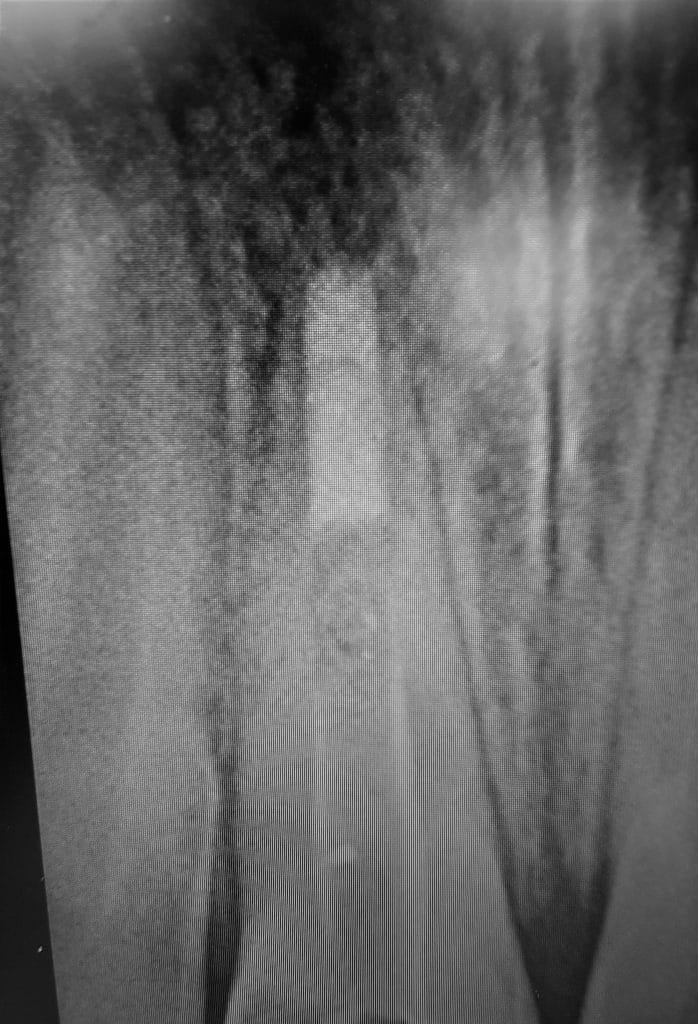

: nonvital tooth

open apex

MTA obturation

Complete obturation